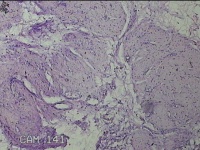

子宫体肌瘤结节

性别

女

年龄

32岁

临床诊断

子宫肌瘤 疤痕子宫

一般病史

发现子宫肌瘤数月余。

标本名称

大体所见

灰白色圆柱形条索状组织10x7.5x1.8㎝一堆,切面均为灰白色结节状或编织状,质中。

图2